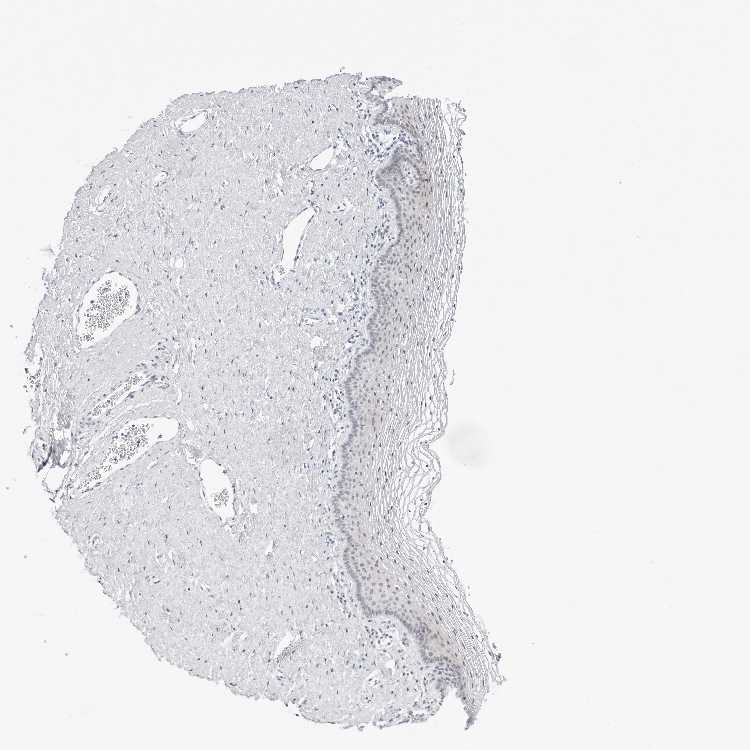

TISSUE PRIMARY DATA VAGINA Show tissue menu

Vagina

VAGINA - Antibody stainingi

Antibody staining in the annotated cell types in the current human tissue is reported as not detected, low, medium, or high, based on conventional immunohistochemistry profiling in selected tissues. This score is based on the combination of the staining intensity and fraction of stained cells.

Each image is clickable and will lead to virtual microscopy that enables deeper exploration of all samples and also displays staining intensity scores, fraction scores and subcellular localization as well as patient and tissue information for each sample.

Antibody HPA027120Antibody HPA027125Antibody HPA027268

Squamous epithelial cells MediumMediumNot detected